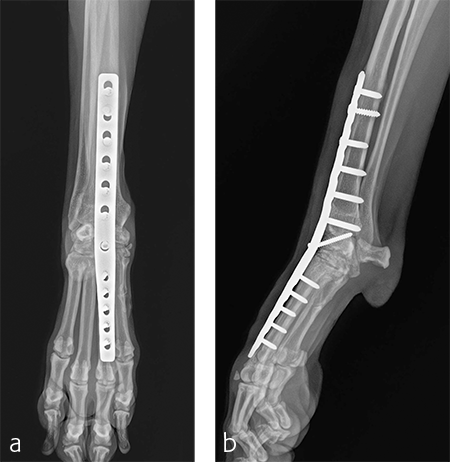

The patient was returned to normal activity 4 months after surgery. Radiographic examinations at 6 and 6.5 months after surgery revealed stable implants and fusion of the carpus (Fig 7 and 8). Functional outcome was excellent 1 year postoperatively. The patient had returned to full weight-bearing without lameness and the carpus was pain-free and stable.